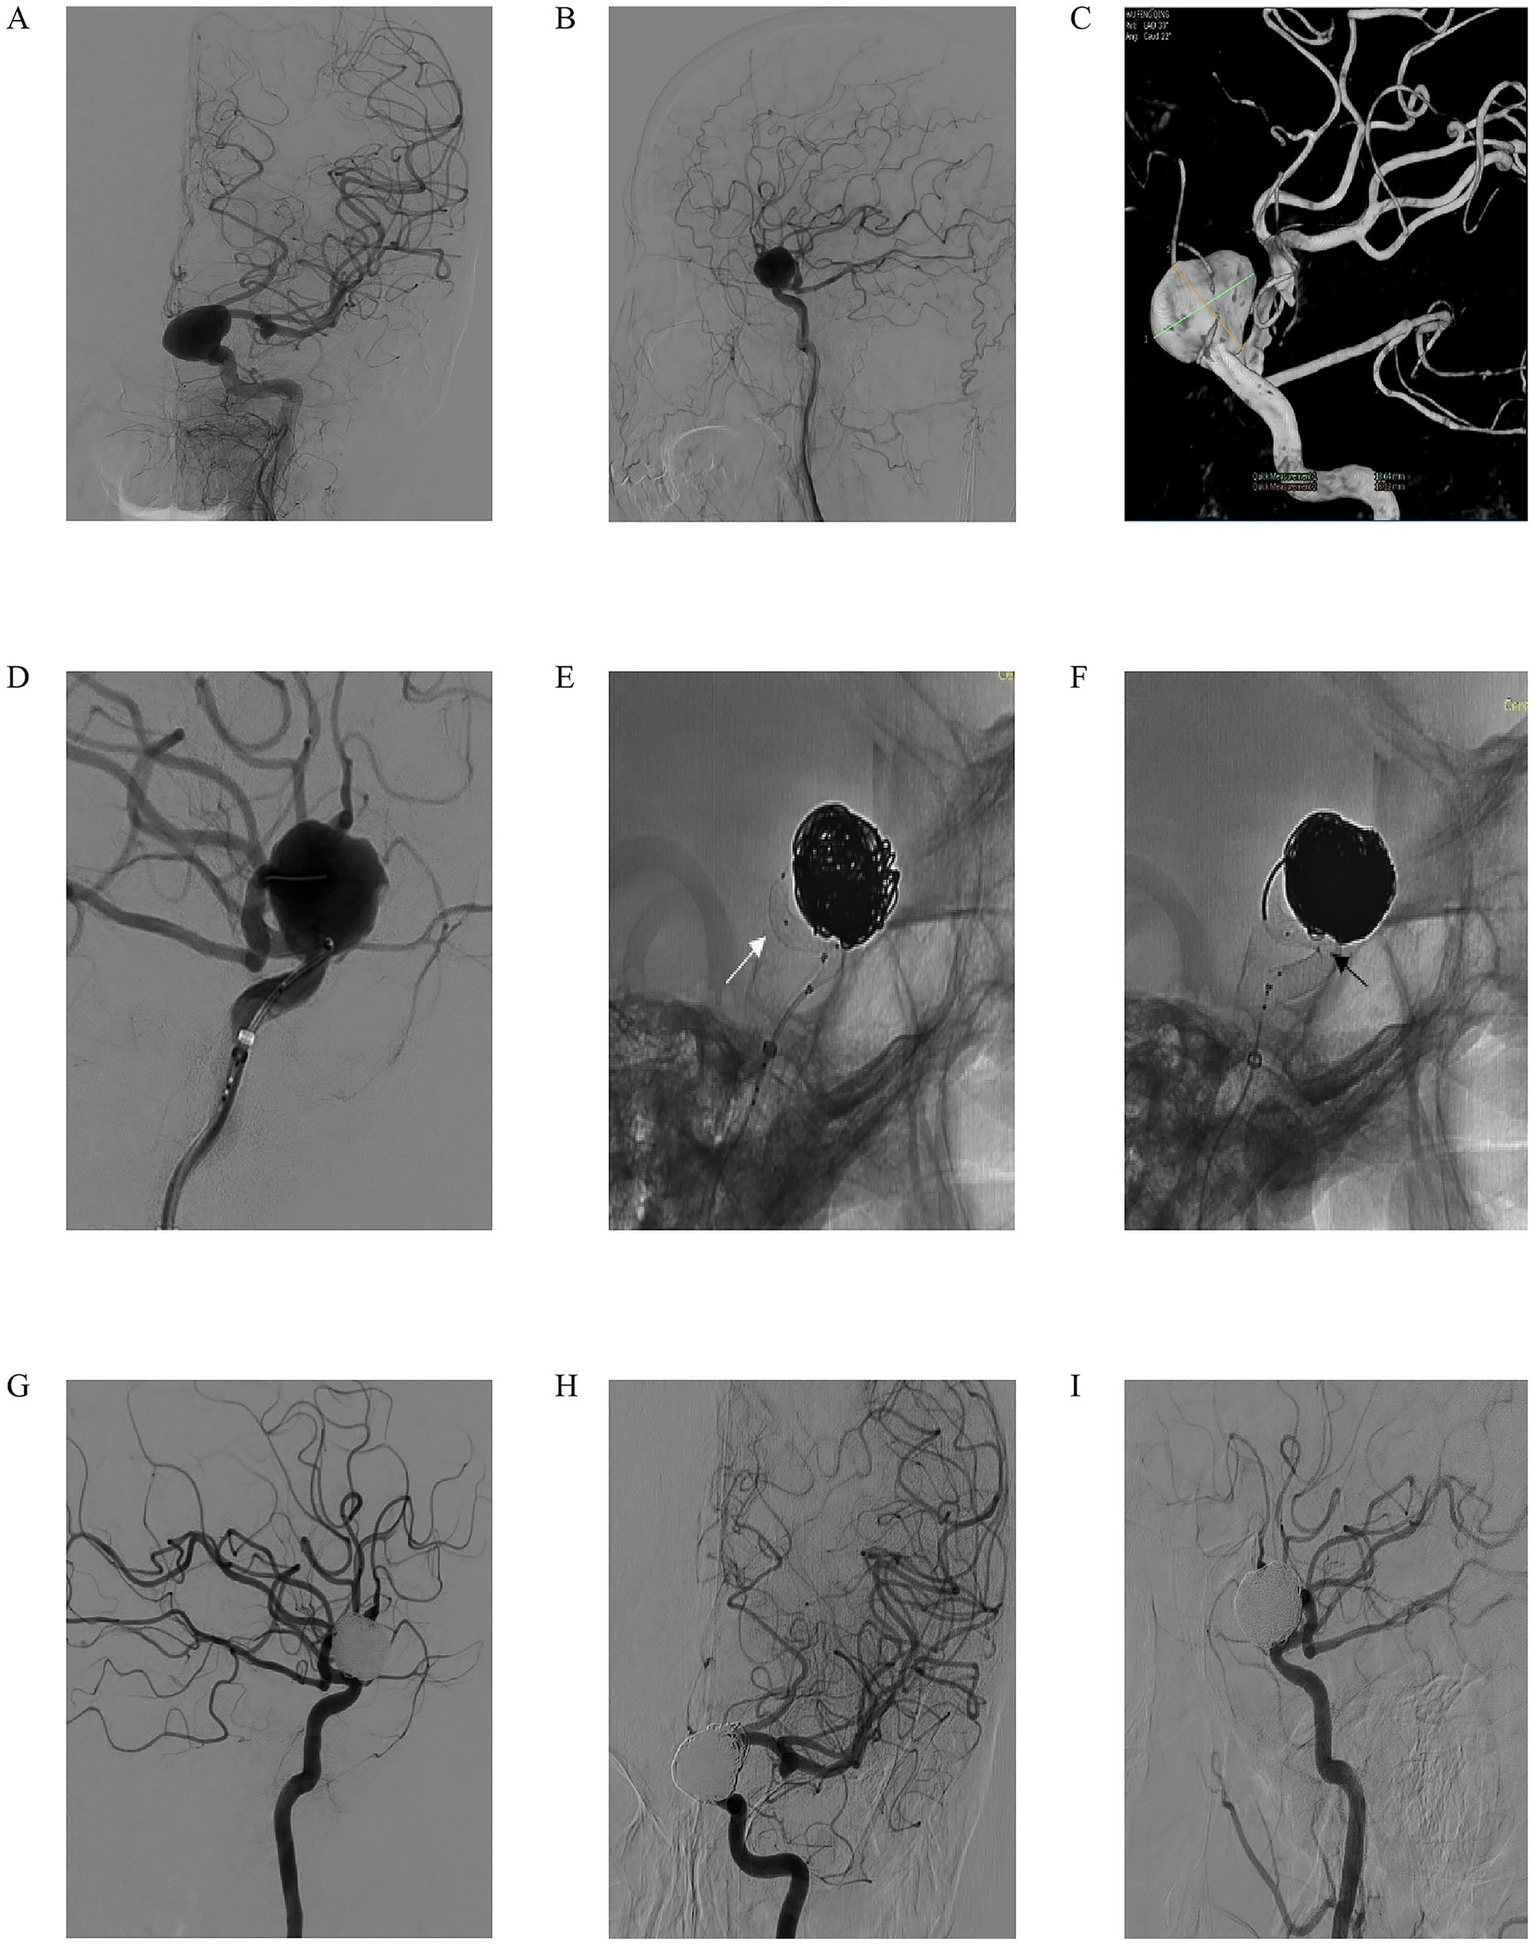

We present the case of a 59-year-old woman who presented with progressive left eye vision loss over 1 year, which worsened in the past week. Neurological examination showed normal ocular movements, intact pupillary light reflexes, and preserved limb mobility. Imaging evaluation included L-ICA DSA in anteroposterior and lateral views (Figures 2A,B), which revealed a saccular aneurysm in the C5-6 segment with a prominent “jet sign,” an indicator of hemodynamic stress. A 3D-DSA reconstruction (Figure 2C) confirmed an irregularly shaped giant aneurysm measuring 18.64 mm × 16.22 mm. During endovascular intervention, a working-angle projection (Figure 2D) guided the advancement of an intermediate catheter and the microcatheter XT27 to the middle cerebral artery. The Lattice FD-MB was deployed in a semi-released state (Figure 2E, white arrow indicating the “lantern-shaped” configuration within the Lattice), allowing partial coiling of the aneurysm sac. Following full deployment of the Lattice FD-MB (Figure 2F, black arrowheads confirming optimal wall apposition at vascular bends), immediate post-procedural DSA (Figure 2G) confirmed complete exclusion of the aneurysm from circulation, with no contrast filling. At the 4-month follow-up, DSA (Figures 2H,I) demonstrated complete aneurysm occlusion, patency preservation of the parent artery without stenosis, and successful hemodynamic reconstruction. This case illustrates the efficacy of Lattice FD-MB in achieving anatomical cure for complex giant aneurysms while preserving distal perfusion, with favorable short-term outcomes.

Figure 2. A 59-year-old woman reported a decrease in visual acuity of her left eye for 1 year, which had aggravated over the past 1 week. In the specialized physical examination, the movement of the eyeball was normal, the light reflex was normal, and the limb movement was normal. (A,B) Left ICA digital subtraction angiography (DSA) in anteroposterior (A) and lateral (B) views demonstrating a giant saccular aneurysm with a prominent “jet sign” (arrow), indicative of hemodynamic stress. (C) Three-dimensional DSA reconstruction confirming the irregular morphology of the giant aneurysm, measuring 18.64 mm × 16.22 mm; (D) Working-angle projection during intervention guiding the advancement of an intermediate catheter and a microcatheter (XT-27) to the middle cerebral artery; (E) The Lattice FD-MB deployed in a semi-released state (white arrow indicating the characteristic “lantern-shaped” configuration), allowing for partial coiling of the aneurysm sac; (F) Full deployment of the Lattice FD-MB, with black arrowheads confirming optimal wall apposition at critical vascular bends; (G) Immediate post-procedural DSA showing complete exclusion of the aneurysm from circulation with no evidence of contrast filling; (H,I) Four-month follow-up DSA in anteroposterior (H) and lateral (I) views confirming complete aneurysm occlusion, patency of the parent artery without stenosis, and successful hemodynamic reconstruction.